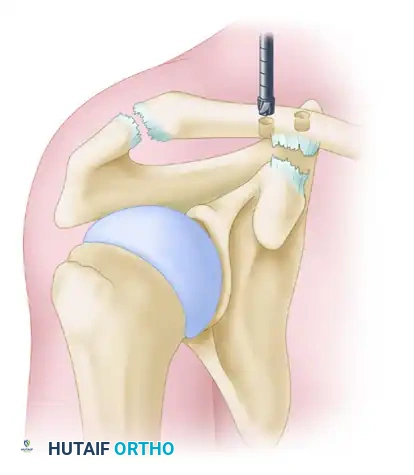

3. Distal Clavicle Resection (Mumford Procedure)

To prevent postoperative AC joint arthrosis and impingement, a distal clavicle excision is performed.

* Resect the distal 10 mm of the clavicle using an oscillating saw.

* Crucial Step: Bevel the inferior aspect of the resected clavicle. This prevents impingement of the clavicle against the acromion or the graft during shoulder elevation.

5. Clavicular Tunnel Placement

Accurate tunnel placement is the most critical step in recreating the native anatomy.

* Conoid Tunnel (Posterior/Medial): Drill the first tunnel 45 mm medial to the native distal clavicular articular surface. Note: If a 10 mm distal clavicular resection has already been performed, this tunnel should be placed 35 mm from the new cut edge. Position this tunnel slightly posterior on the clavicle to recreate the native conoid insertion.

* Trapezoid Tunnel (Anterior/Lateral): Drill the second tunnel 15 mm lateral to the conoid tunnel. Position this tunnel slightly anteriorly to recreate the native trapezoid insertion.

* Use an appropriate cannulated reamer (typically 5.0 mm to 6.0 mm, depending on graft diameter) over a guide pin.

Mazzocca anatomic coracoclavicular reconstruction: Incision and precise tunnel placement. The posterior tunnel recreates the conoid ligament, while the anterior tunnel recreates the trapezoid ligament.